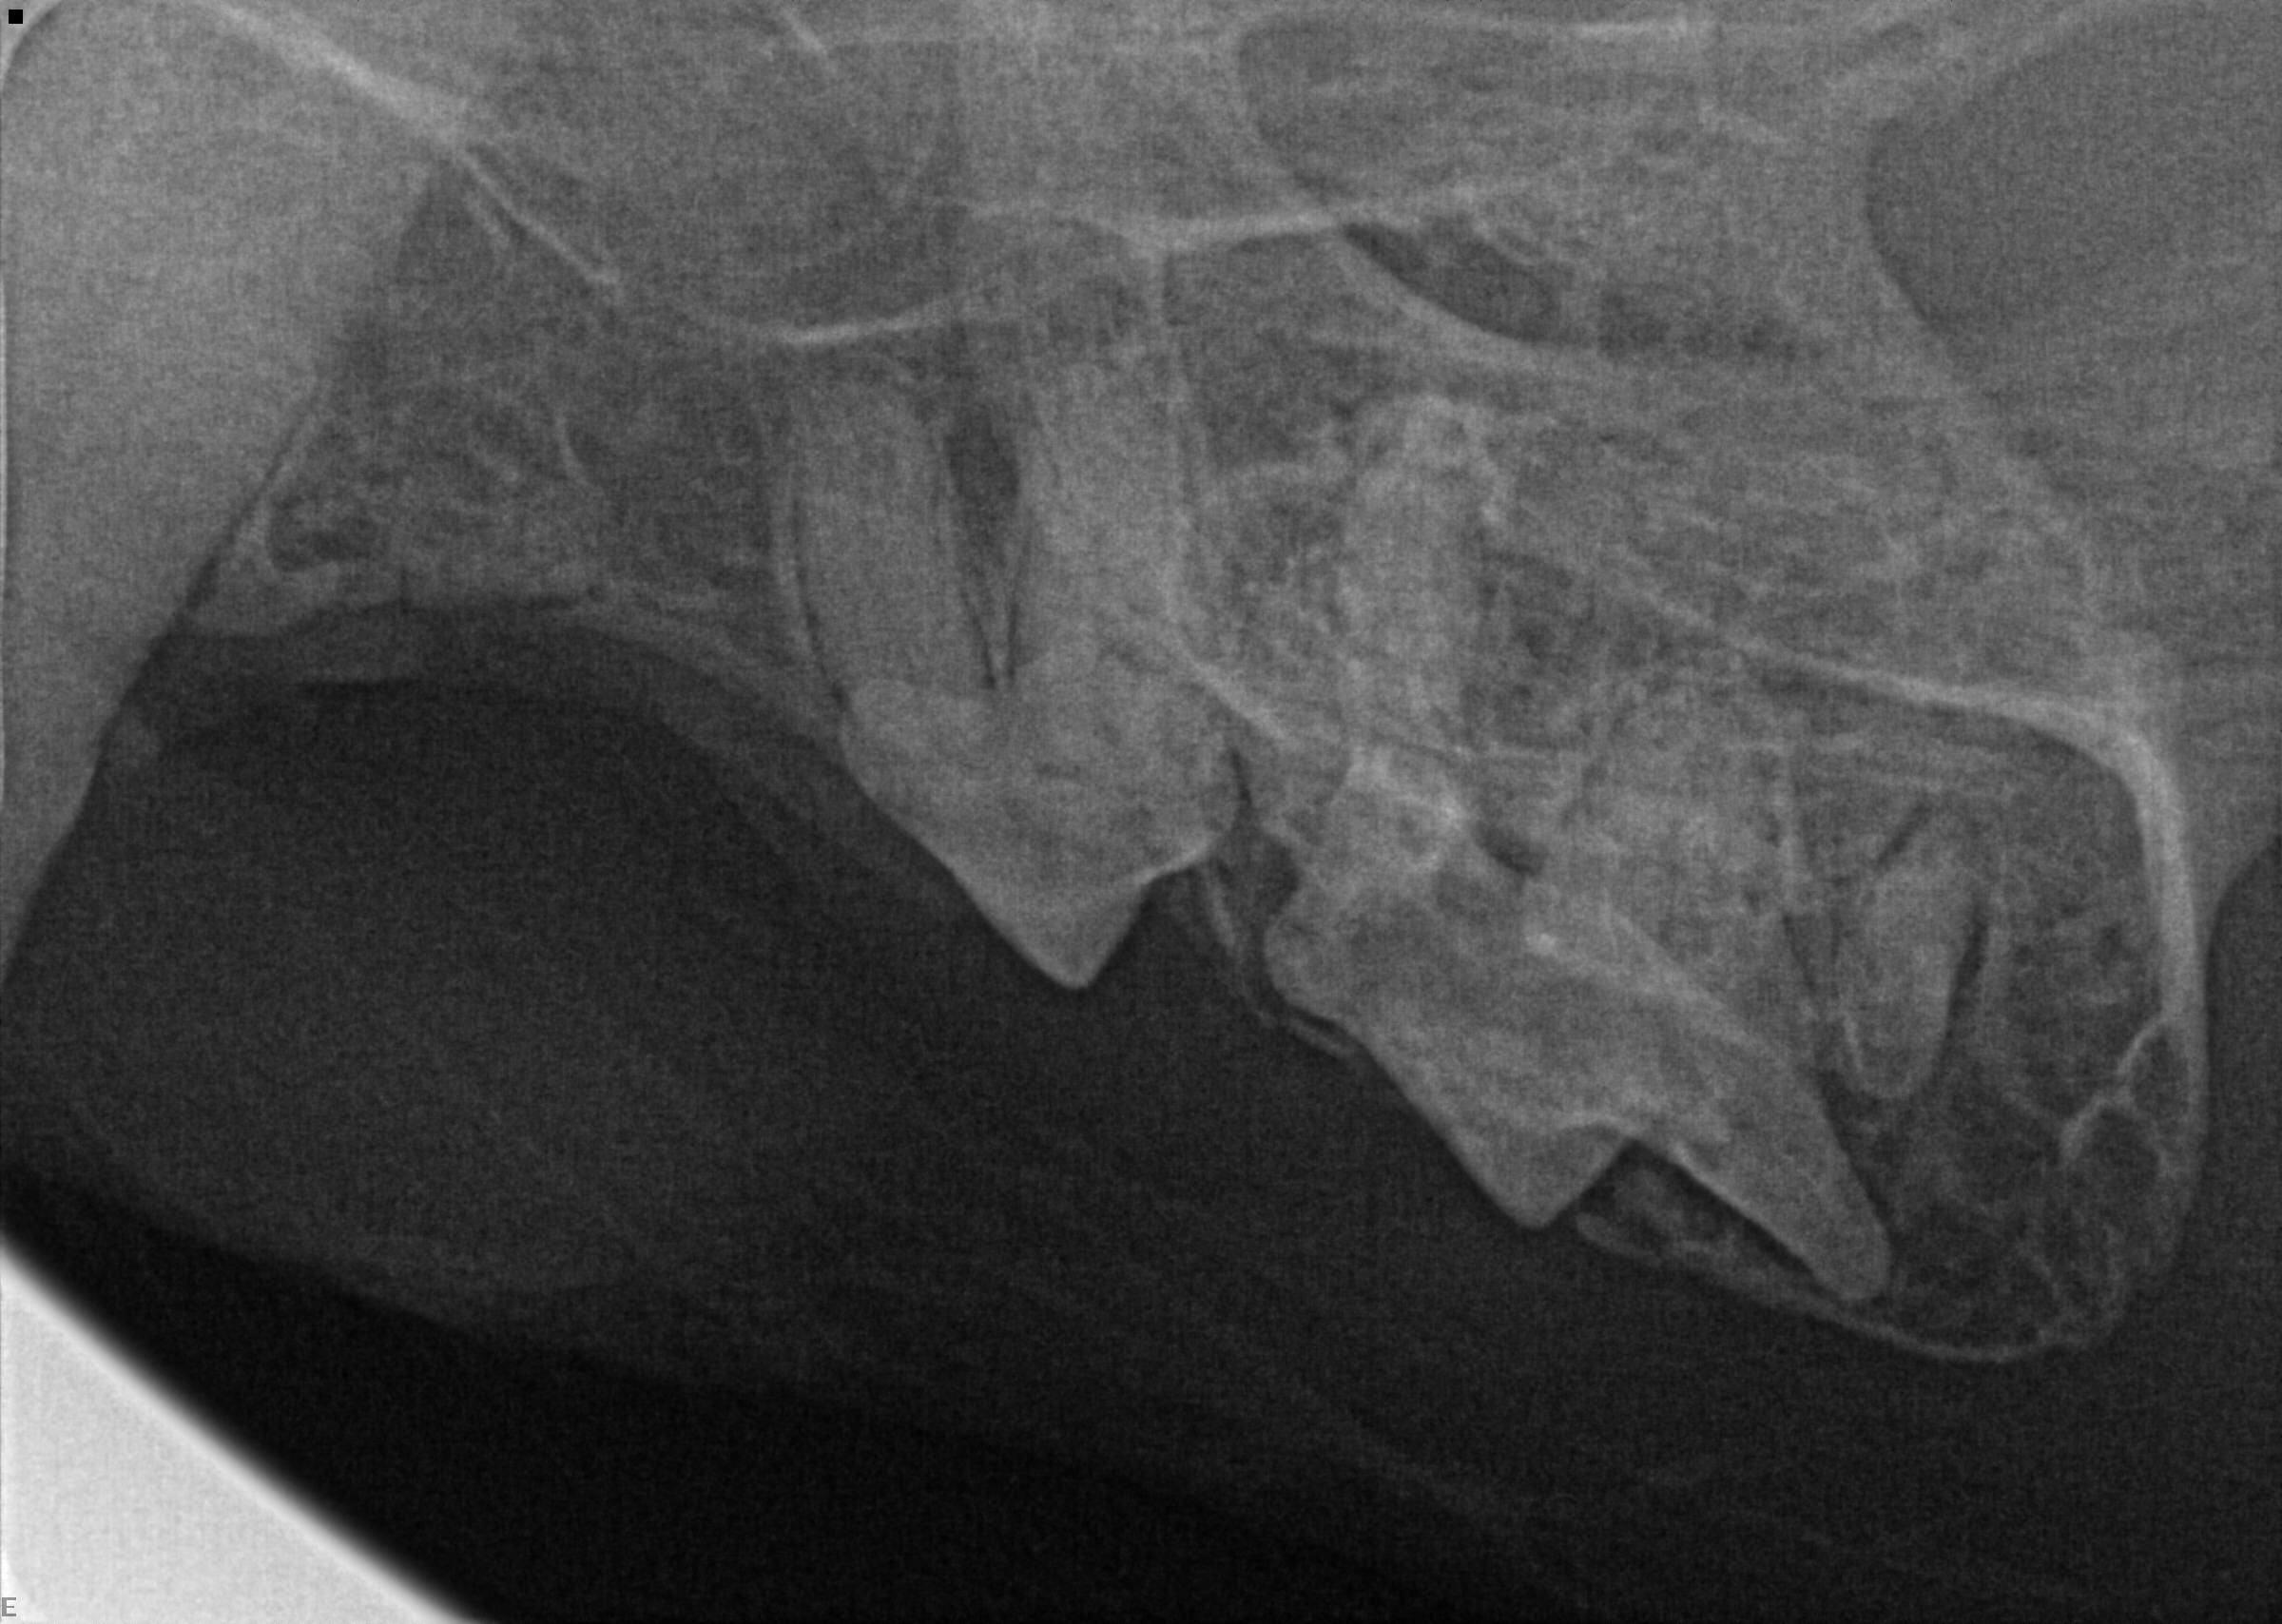

Cat Teeth Xray . 50k views 13 years ago. Superimposition of the nasal ridge of the incisive bone over the incisor roots has been. Becoming familar with the techniques required for dental radiology and radiography can, therefore, be greatly beneficial. Retained tooth root fragments in dogs and cats are a common radiographic finding. Information crucial to the diagnosis and treatment of feline oral diseases can be ascertained using dental radiography and the inclusion of this technology has been shown to be the best way to improve a dental practice. The dotted lines show the trajectory of the zygomatic arches on both radiographs, illustrating how more superimposition with structures of interest occurs in the intraoral view than in. Sign up for my monthly newsletter at:. 6,7 tooth roots may be retained as a result of poor extraction technique or may be fractured as a result of trauma or tooth resorption.

Evansville Dental Radiographs Dog & Cat Teeth xray

Dental Digital Radiology Cat Dental Xray Cat Teeth Xray Retained tooth root fragments in dogs and cats are a common radiographic finding. Sign up for my monthly newsletter at:. Information crucial to the diagnosis and treatment of feline oral diseases can be ascertained using dental radiography and the inclusion of this technology has been shown to be the best way to improve a dental practice. The dotted lines show. Cat Teeth Xray.

Feline Tooth Resorption Lesions Perth Cat Hospital Cat Teeth Xray Retained tooth root fragments in dogs and cats are a common radiographic finding. The dotted lines show the trajectory of the zygomatic arches on both radiographs, illustrating how more superimposition with structures of interest occurs in the intraoral view than in. Sign up for my monthly newsletter at:. 6,7 tooth roots may be retained as a result of poor extraction. Cat Teeth Xray.